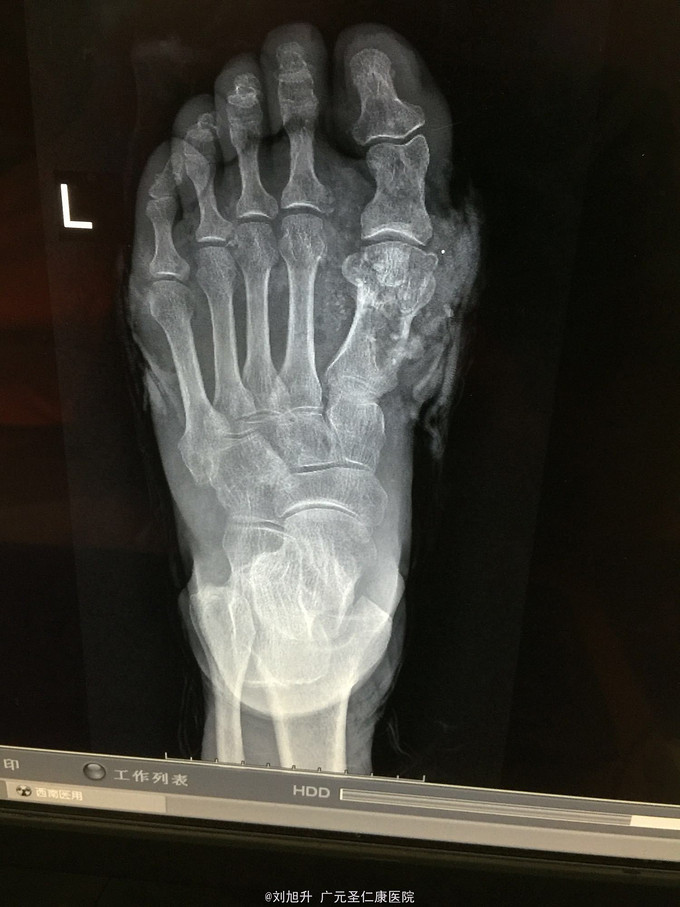

左足背砸伤

患者,男,61岁,因左足背重物砸伤5小时入院